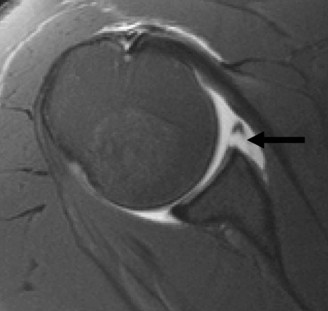

Identify the muscles that compose the force couples in the transverse and coronal planes? CASE 3 A 35-year-old male has had left shoulder pain for 4 months, ever since a low-speed motor vehicle accident (MVA). Physical examination demonstrates preserved range of motion but pain and some weakness with Jobe’s testing. His imaging is shown in Figure 2–8.

Figure 2–8_Reproduced with permission from Stadnick ME. _Partial Rotator Cuff Tears. MRI Web Clinic. 2007 (Apr).

What is the most likely diagnosis?

Discussion

The correct answer is (A). These are best diagnosed on an MRI as seen in the imaging provided; addition of intra-articular contrast can further improve this study. Answer B, full-thickness rotator cuff tear, is incorrect as the bursal side of the tendon can be seen to be in continuity. Answer C, a SLAP lesion, will be visualized as a labral tear on a coronal MRI and will be found at the biceps root. Answer D, an ALPSA lesion, will be most clearly seen on an axial MRI. It is a variant of a Bankart lesion where the labrum is displaced medially and inferiorly rolling down the glenoid neck underneath the periosteum.

MRI remains the most popular imaging modality for diagnosing rotator cuff tears. Normal rotator cuff tendon appears dark on both T1 and T2 sequences. Tears may be noted as being full-thickness, articular-sided, bursal-sided, or intrasubstance. They are visualized as a disruption in the regular contour of the tendon and increased signal intensity on T2 sequences. Occasionally, an MR arthrogram may provide additional information regarding a cuff tear, although this is not routinely ordered.

What MRI sequence and plane is best for viewing supraspinatus rotator cuff tears?

The correct answer is (D). T2 sequence causes most soft tissues, including muscle and tendon, to appear dark and inflammation, such as at the site of a tear, to appear bright. This means that if there is a rotator cuff tear, there will be a bright spot along the course of the dark rotator cuff tendon. This is easiest to pick out in the coronal plane because the tendon runs in this plane, allowing one to view the entire supraspinatus tendon and tear in one cut.